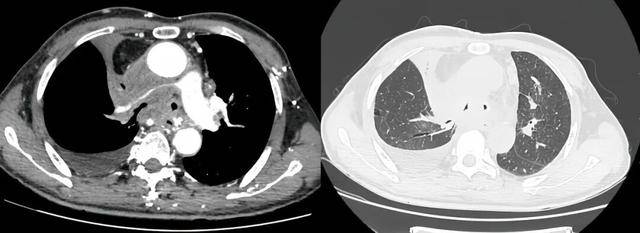

术前受压变窄的右肺动脉和中央气道

手术过程